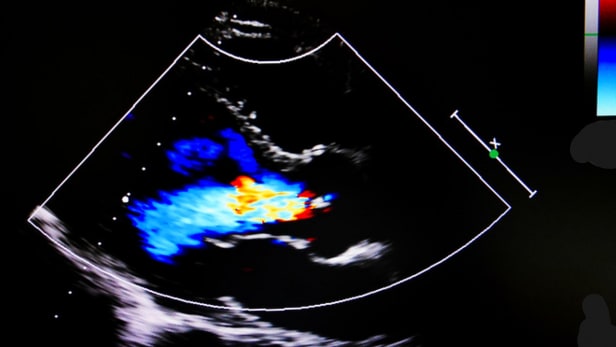

• Regelmässig zu selten eingesetzt wurde die Echokardiographie, so ein erstes Ergebnis (erfasst in 4 Studien, zwischen 54 und 89 Prozent underuse).

• Auch hier taucht die Echokardiographie zuoberst auf, wo laut anderen Studien in bis zu 92 Prozent der Fälle «übertrieben» eingesetzt wurde; dies muss kein Widerspruch sein, teils weil einige Studien andere Ergebnisse zeigen, teils auch, weil eine Methode bei einem Patienten fälschlich, bei einem anderen aber zugleich fälschlich zuwenig eingesetzt werden kann.

Ein Fazit lautet höchstens, dass sich die Hausärzte des Wertes und Nutzens der Ultraschallkardiographie nicht recht sicher sind. Oder wie es die Autoren aus Oxford formulieren: «The use of echocardiography (both underuse and overuse) is consistently poor».